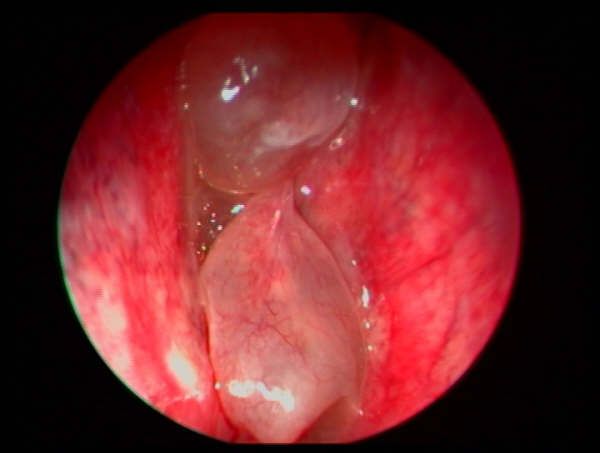

Nuestro servicio de otorrinolaringología en Vigo ofrece atención especializada para el diagnóstico y tratamiento de problemas de oído, nariz y garganta. Trabajamos con un enfoque cercano y profesional para resolver desde molestias comunes hasta patologías más complejas. Valoración de daño auditivo y peritajes.

En nuestra clínica, nos enfocamos en proporcionar soluciones efectivas para una variedad de problemas relacionados con la salud del oído, nariz y senos paranasales. Nuestro objetivo es ofrecer tratamientos avanzados y personalizados a cada paciente.